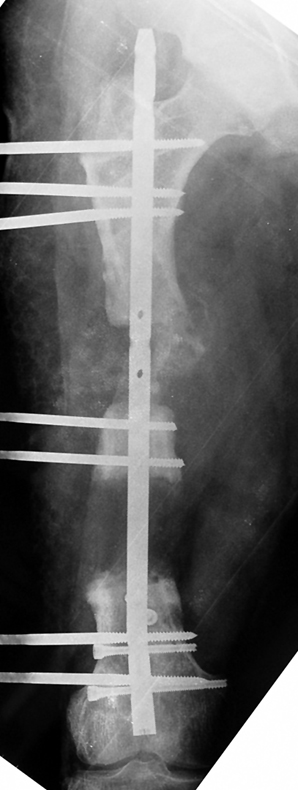

Uygun radikal debridman tüm nekrotik kemik ve yumuşak dokuların çıkartılmasını gerektirir, ve sıklıkla uzuvda instabiliteye neden olur. Kalan kemik ve yumuşak doku defektinin bir şekilde fiksasyonu ve rekonstrüksiyonu gereklidir. İlizarov’un ortaya koyduğu distraksiyon osteogenezi yöntemi, kaynamanın elde edilmesi, deformitenin düzeltilmesi, bacak boy eşitsizliğinin giderilmesi ve segmental defektlerin rekonstrükte edilmesi için başarıyla kullanılmaktadır.

Eksternal fiksatör ile geçen süre (eksternal fiksasyon indeksi), gereken distraksiyon miktarına bağlıdır ve bu süre boyunca bazı komplikasyonlarla karşılaşılabilir. Distraksiyon dönemi sona erdikten sonra, distraksiyon süresinin iki katını aşan konsolidasyon döneminde hastalar eksternal fiksatörü zorlukla tolere edebilirler. Yeterli konsolidasyon sağlanmadan eksternal fiksatör çıkartılırsa ise kırıklar, deformite ve kısalık oluşabilir. Hastanın fiksatör ile birlikte geçirdiği sürenin azaltılması ve böylece hasta konforunun ve aktivite düzeyinin arttırılması için intramedüller çivi üzerinden uzatma yöntemi uygulanmaktadır. Bu yöntemde distraksiyon dönemi sona erdiğinde kemiğin içindeki çivi statik olarak kilitlenmekte ve eksternal fiksatör çıkartılmaktadır. Stabilizasyon intramedüller çivi tarafından sağlandıktan sonra konsolidasyon dönemi gerçekleşmektedir. Bu şekilde hem eksternal fiksatörün uzun süre kalmasından hem de erken çıkartılmasından kaynaklanan komplikasyonların önüne geçilmektedir.